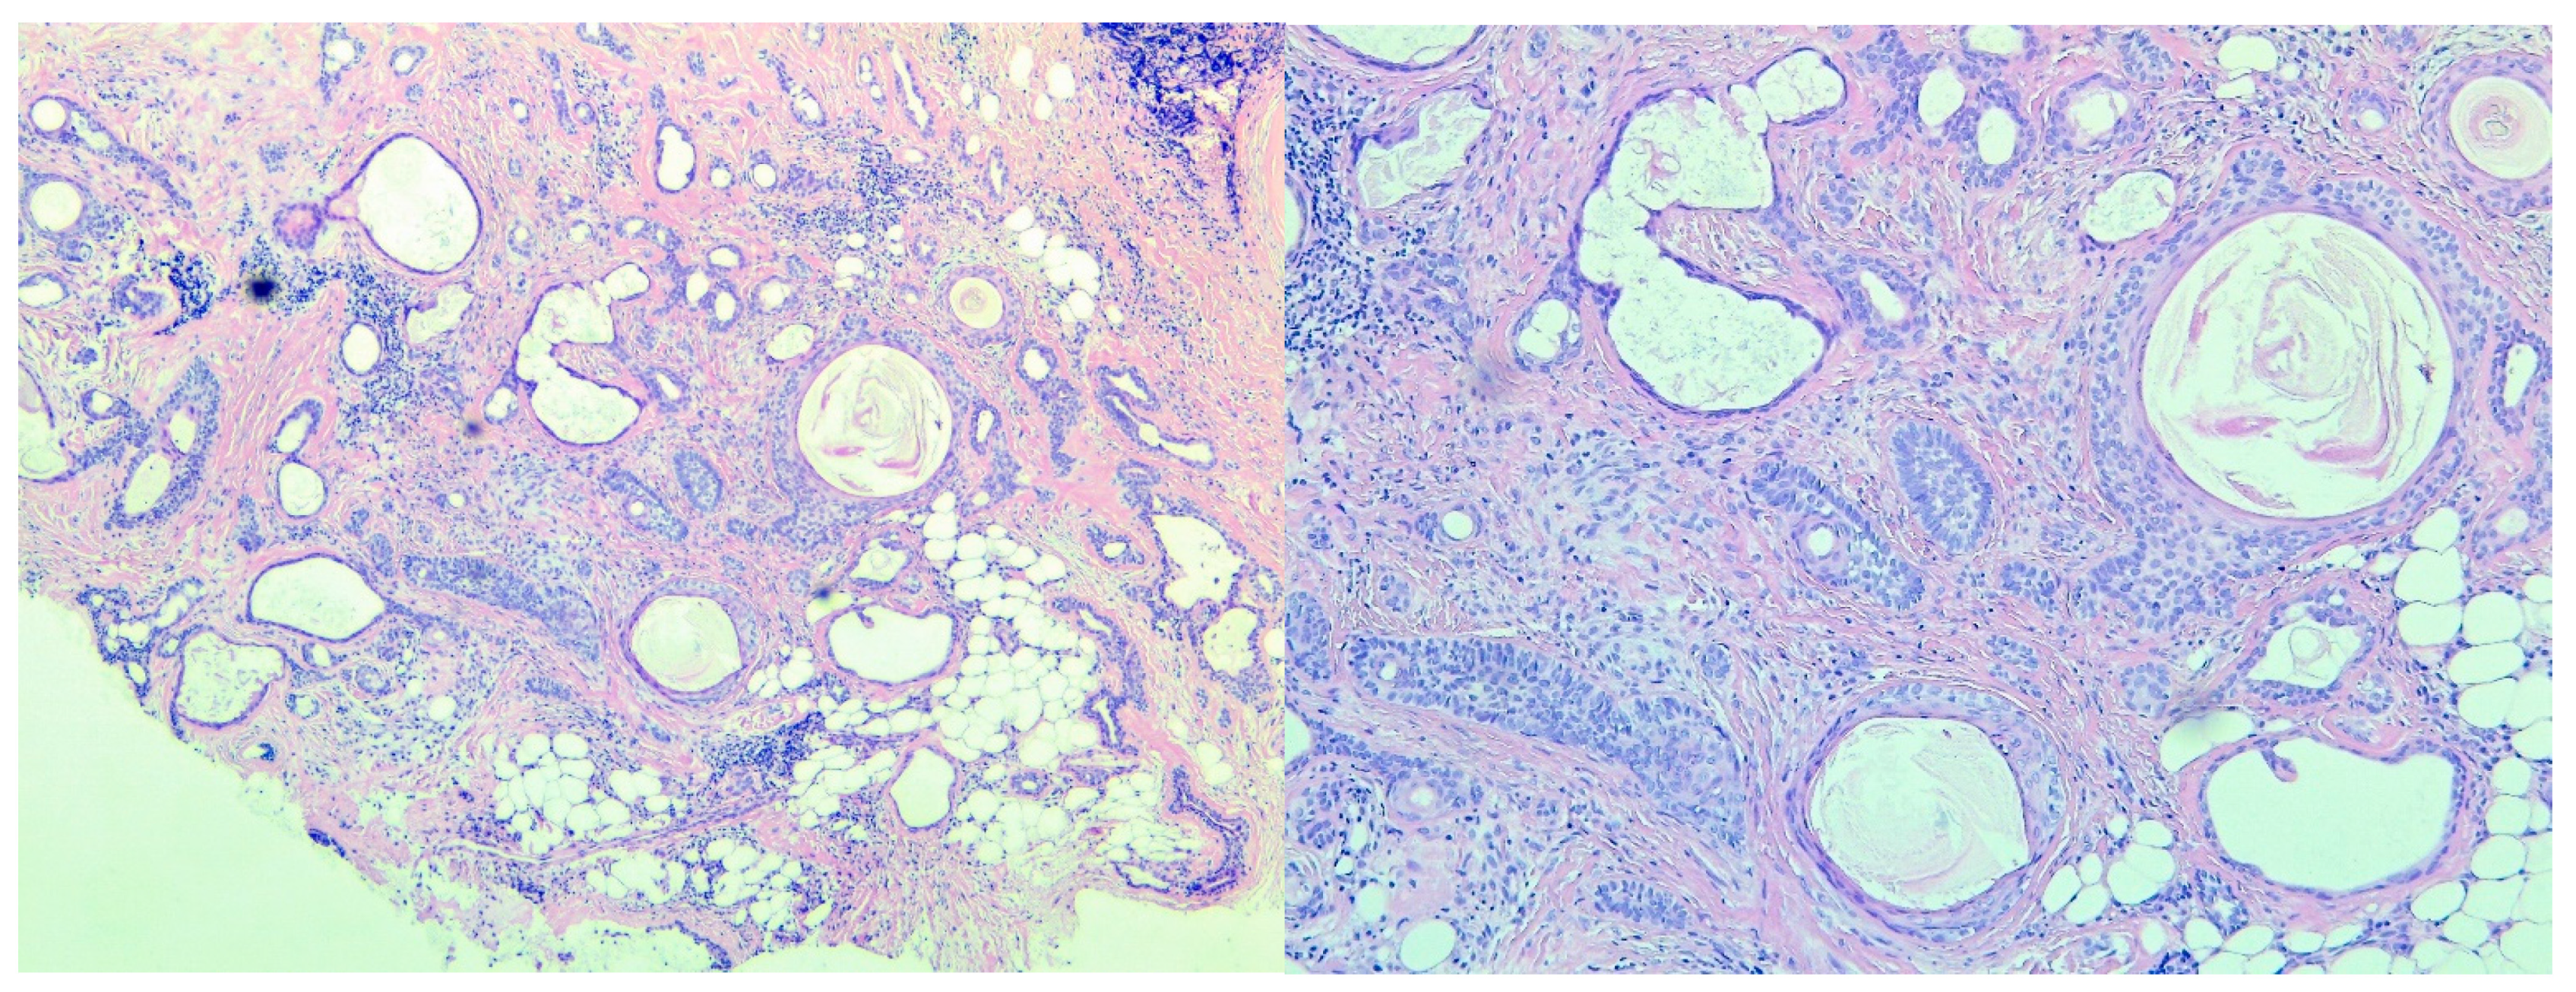

Figure 4.

(A) Tubular structures and solid areas in a mixochondroid background. (B) Infundibular cysts in various sizes with corneocytes in lamellar pattern. (C) Follicular germlike structures, (small aggregations of germinative cells with peripheral palisading, with or without associated whorls of delicate collagen bundles and thin fibroblasts). (D) Comma/tadpole shaped ducts; syringoma like eccrine structures. (E) Cells resembling those of the internal epithelial sheath (trichohyalin granules).

The follicular differentiation was determined by the presence of infundibular cysts (cystlike structures lined by a stratified squamous epithelium that contains a granular layer and corneocytes in lamellar pattern) (Figure 4B), basaloid metrical cells, trichohyalin granules, follicular germlike structures, and trichilemmal differentiation (palisaded pale or clear columnar cells often associated with a basal membrane, often with nuclei at the pole opposite to the basement membrane, indicating follicular differentiation toward the outer sheath at the bulb) (Figure 4C,E).